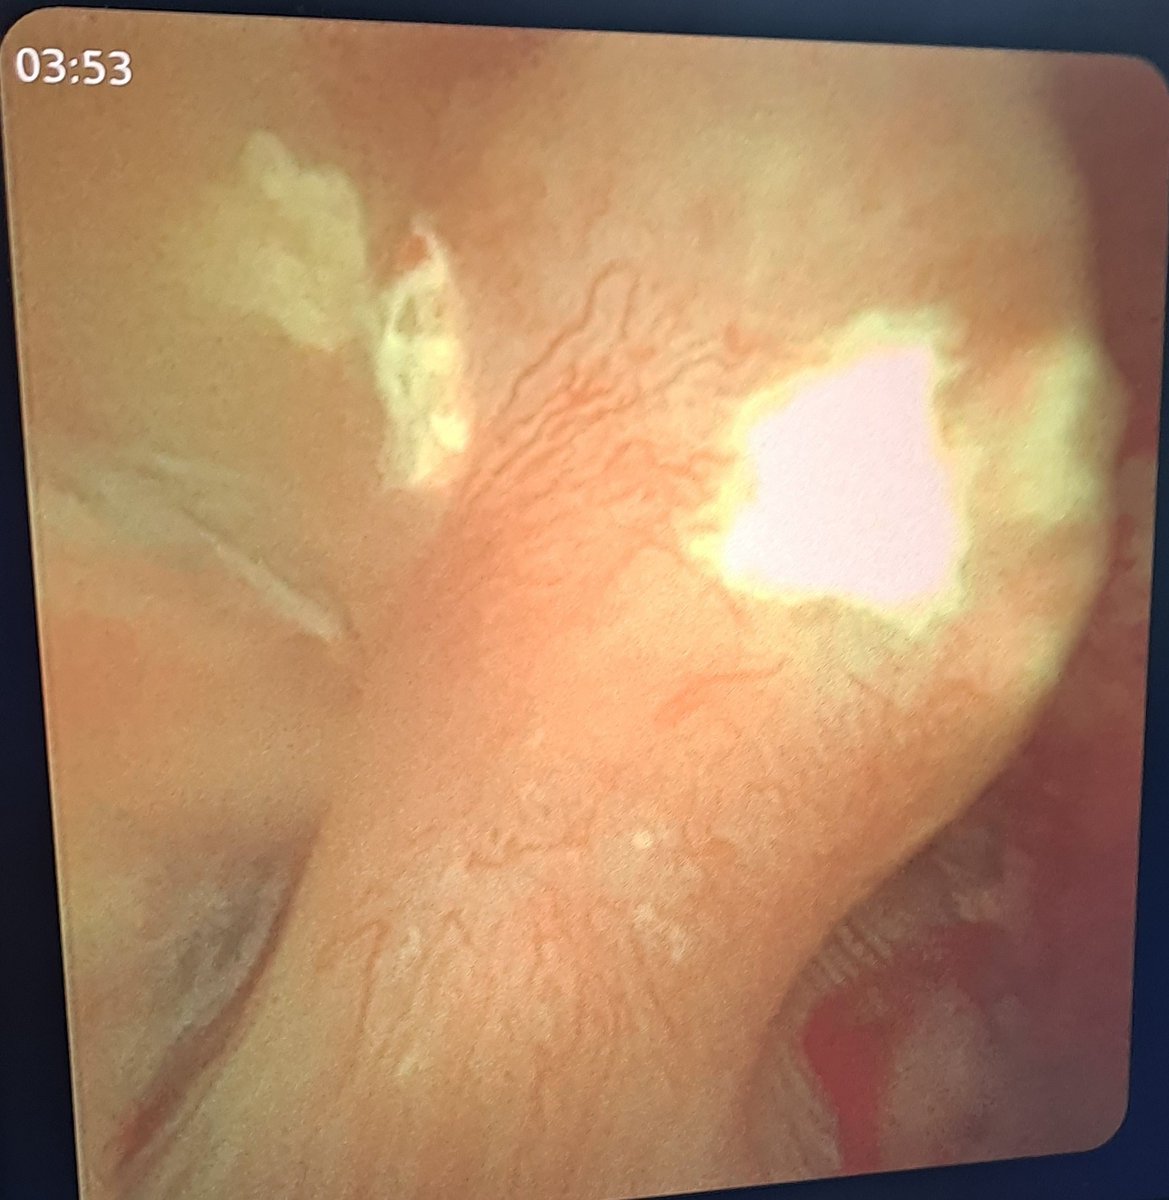

Randall's plaques, viewed by Flexible ureterorenoscopy. (جير راندال) هو ترسبات داخل جيوب الكلى يشتبه بكونها متسببه فى تكوين حصوات الكلى. Randy's ㅤb د. محمد بكر مسالك بوليه

Randall's plaques, viewed by Flexible ureterorenoscopy.

(جير راندال) هو ترسبات داخل جيوب الكلى يشتبه بكونها متسببه فى تكوين حصوات الكلى.